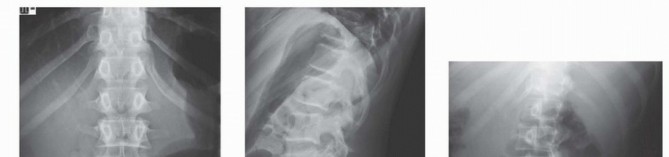

In patients with radicular symptoms, unilateral involvement is more common. Flattening of the lumbar lordosis is commonly seen on physical examination (

FIG 2

). A palpable step in the spinous processes is often seen in isthmic spondylolisthesis.

FIG 2 • A 14-year-old boy diagnosed with spondylolisthesis with flattening of the lumbar lordosis.